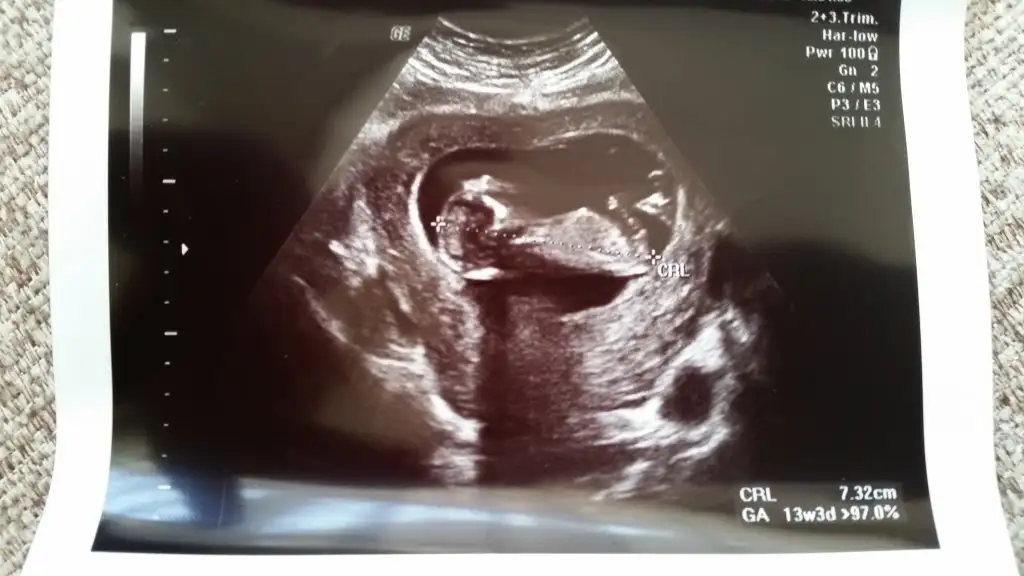

Mervecim bebişin hayırlı olsun,sağlıkla kucağına alırsın inşallah.bir kız haberi de benden,benim de ikinci bebeğim,ilki kızdı bu da kızmış.hayırlısı,sağlıklı sıhhatli olsunlar da.dün dr gittim 14+2de ikili tarama sonucum gelmiş,ona bakarken bebişin de %99 kız olduğunu söyledi,bende gördüm.ilk kızım gibiydi.sen nuba göre kız demiştin,bir erkek,bir kız yorumu olmuştu.Kızçem geliyor.İnşallah herkes en kısa zamanda öğrenir

Kızlar bana da yorum yapabilirmisiniz belli oluyor mu bilmiyorum ama açıkçası ben pek anlamıyor bebisim fotoda 12+4 haftalık tüp bebekle oldu sizce cinsiyeti nedir doktor ancak 16. Haftada söyleyebilirim dedi 12 haziranda bir daha ki kontrolüm çok merak ediyorum lütfen yardımcı olun

Kızlar bana da yorum yapabilirmisiniz belli oluyor mu bilmiyorum ama açıkçası ben pek anlamıyor bebisim fotoda 12+4 haftalık tüp bebekle oldu sizce cinsiyeti nedir doktor ancak 16. Haftada söyleyebilirim dedi 12 haziranda bir daha ki kontrolüm çok merak ediyorum lütfen yardımcı olunEki Görüntüle 1528009

Bariz belli erkek diyorum ben...belli olunca lutfen yazarsaniz